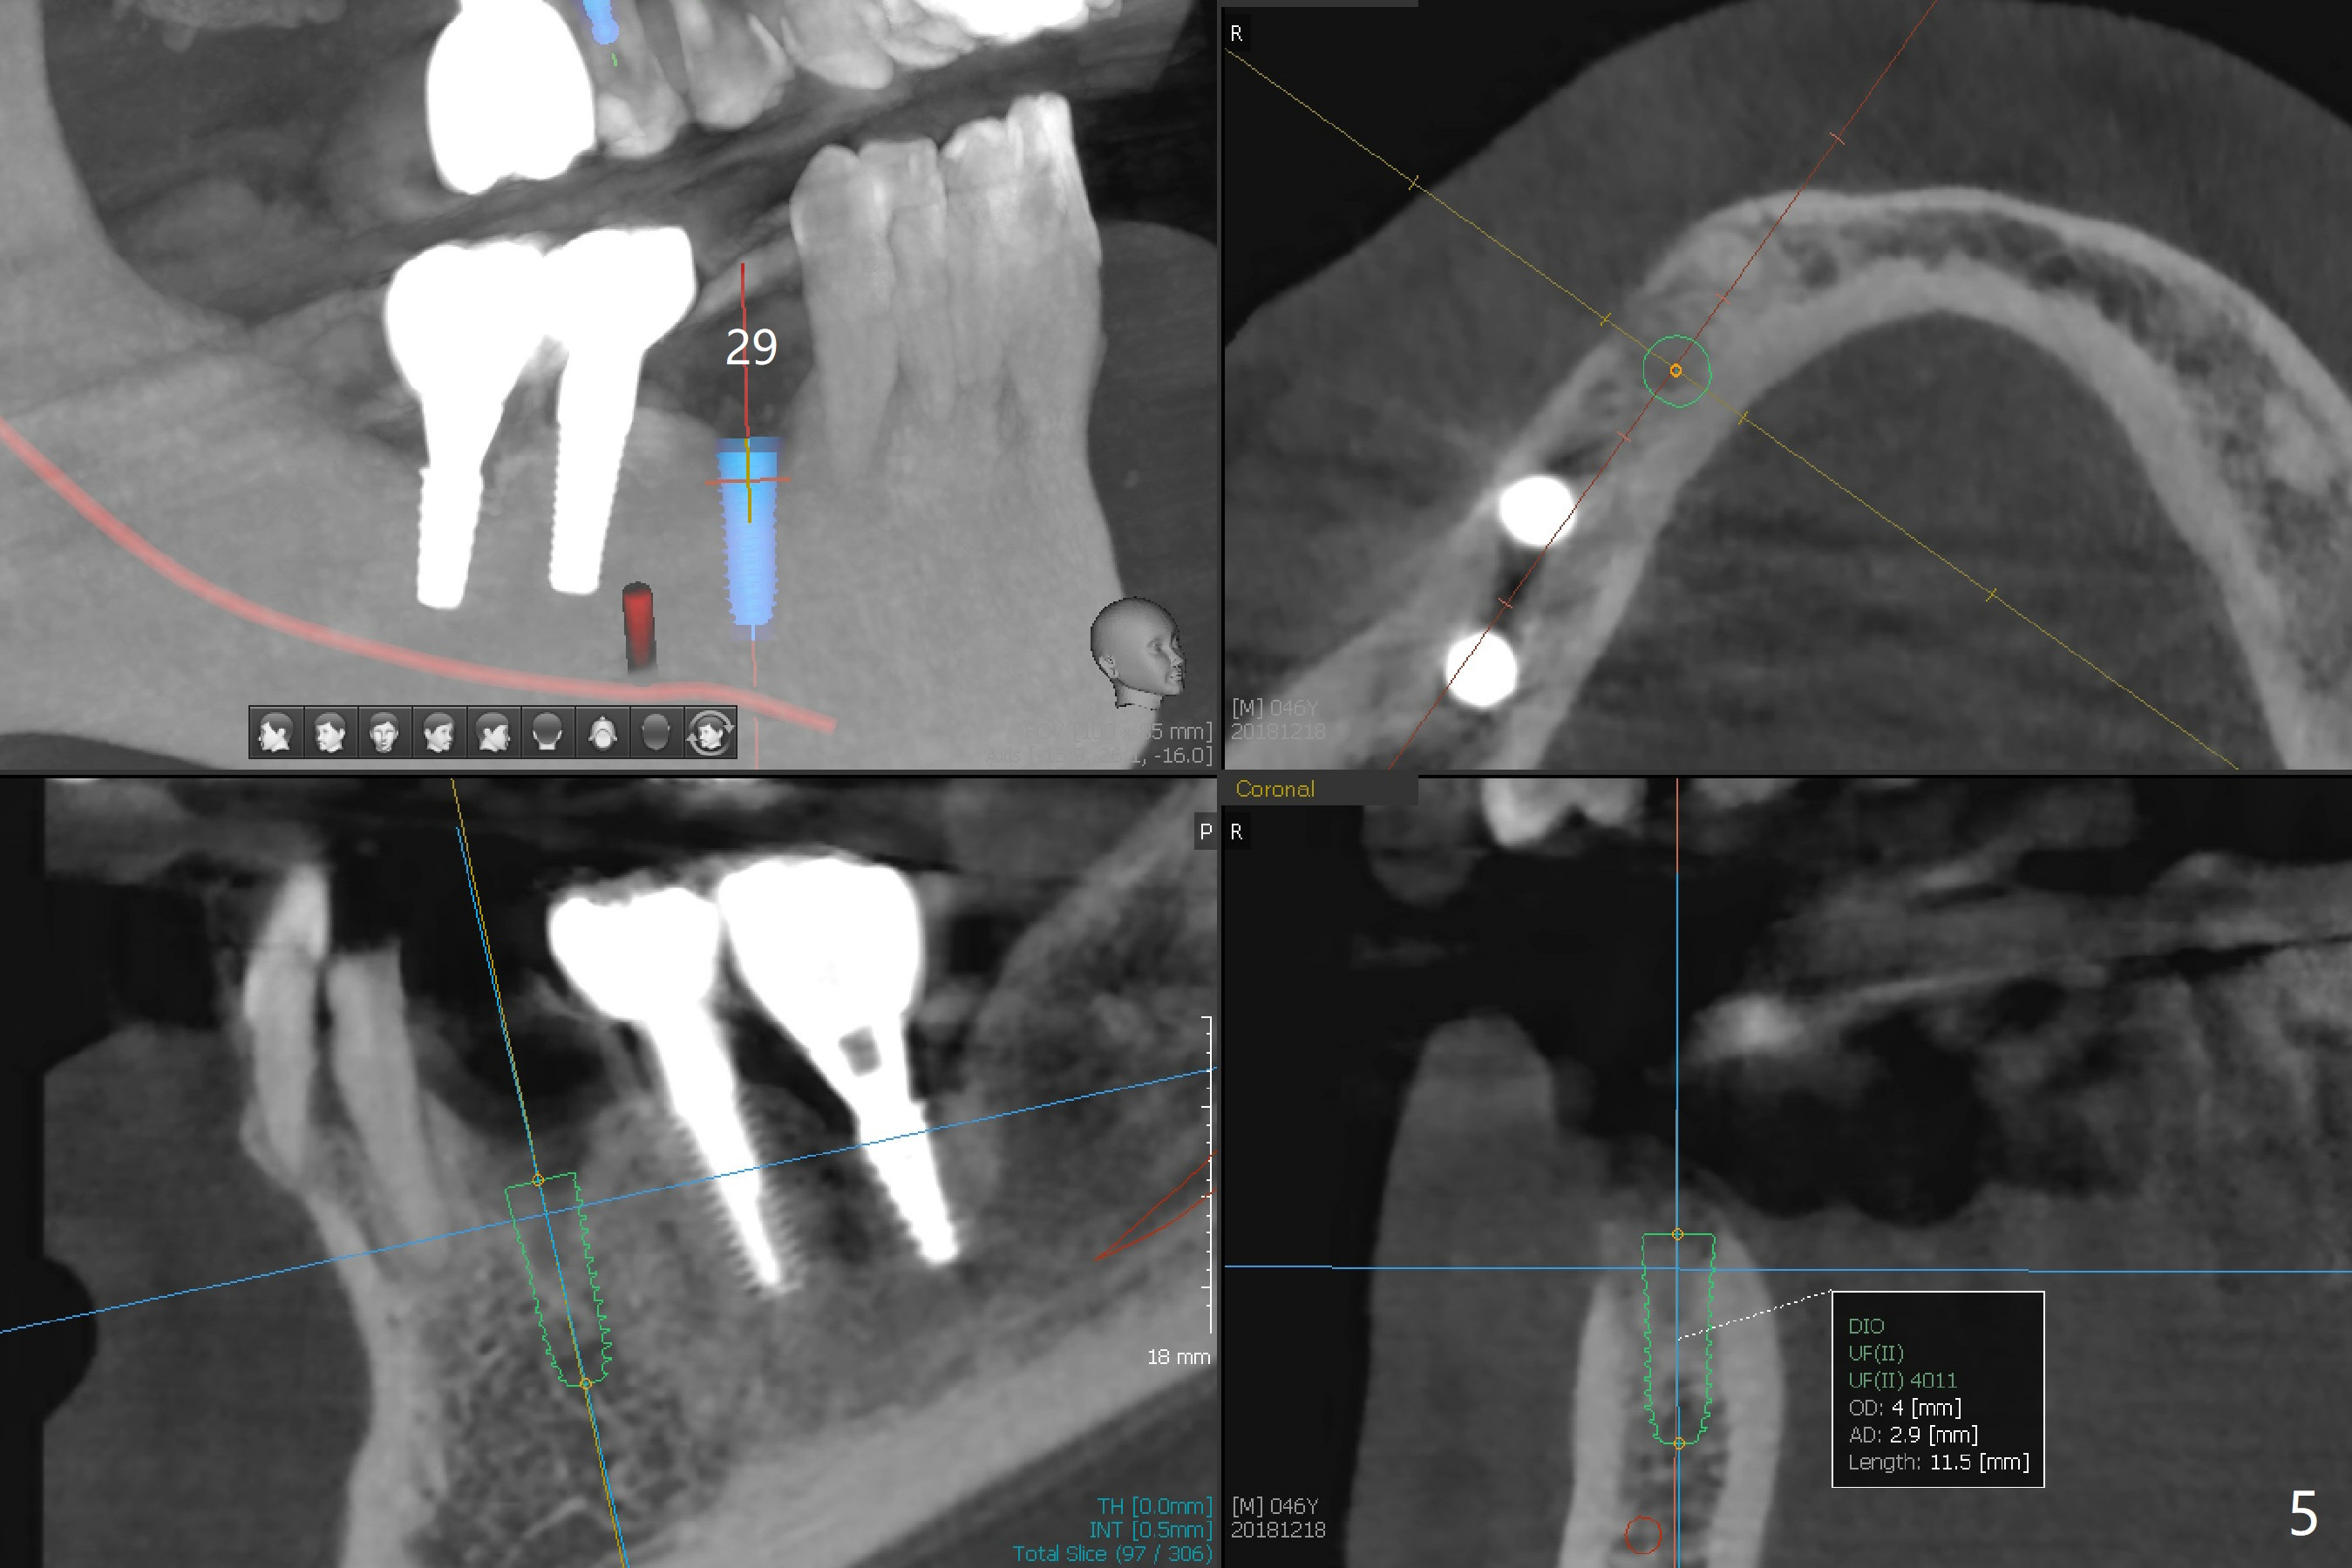

A 46-year-old man requests immediate implants at #4 and 5 because of pain associated with advanced periodontitis. Implants at #15 and 29 were removed with bone graft 4 months earlier (Fig.1). All of the 4 implants will be placed with guide. When 3.5 mm implants are placed at #4 and 5, they appear to be too close to each other (Fig.2). It is alright when the diameter changes to 3.0 mm (Fig.3). While a 5x10 mm implant will be placed at the 2nd stage (Fig.4), a 4x11.5 mm one will be placed in the same appointment as #4 and 5 (Fig.5).